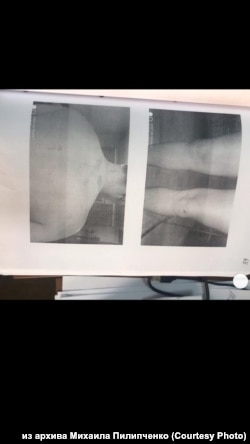

Побои Михаила Пилипченко, зафиксированные судмедэкспертом

– Конечно, я, получается, главный свидетель. Не исключаю, что именно из-за этого на меня уголовное дело завели – репутацию как свидетелю испортить. 17 июня меня вызвали как свидетеля. А буквально через несколько дней уже как подозреваемого опрашивали. Плюс следователь мне "забыла" выдать направление на судмедэкспертизу, а без нее ты побои не снимешь так, чтобы суд это принял. В итоге я только через месяц их снял, когда гематомы уже спали, синяки уже проходили. Статусу подозреваемого я уже не удивился, потому что следователь, еще опрашивая меня по убийству Ильи, заявила, мол, сейчас на тебя 318-ю статью откроем. Так и сказала: "Ты виновен!" Следователь вела даже первый опрос как обвинитель, пыталась меня обвинить постоянно, когда я давал свои показания, коверкала мои слова, пыталась написать их по-другому, чтобы росгвардейцы смотрелись белыми и пушистыми. Постоянно поправлял то, что мне на подпись давали, просил: "Пишите то, что я вам говорю, не надо сочинять". Во время общения со следователем я это понял, когда мне зачитывали обвинение, когда меня начали опрашивать, когда она пыталась исковеркать мои слова. В общем, сразу было видно, как настроены выгородить полицейских, а нас с Ильей сделать виноватыми во всем. Если бы мы общественный резонанс не создали, не выложили бы всю запись видео целиком в ютьюбе, не привлекли бы общественников, то, скорее всего, меня бы уже давно посадили в тюрьму. А Илью бы выставили нападавшим и даже о халатности бы не завели дело на росгвардейца. Даже сейчас стрелявший росгвардеец повторяет версию, что, мол, Илья сам застрелился. Хотя уже и видео есть, и показания охранника, и траектория пули не бьется с его "версией" – сквозь руку охранника, в спину Ильи. Это же физически невозможно!